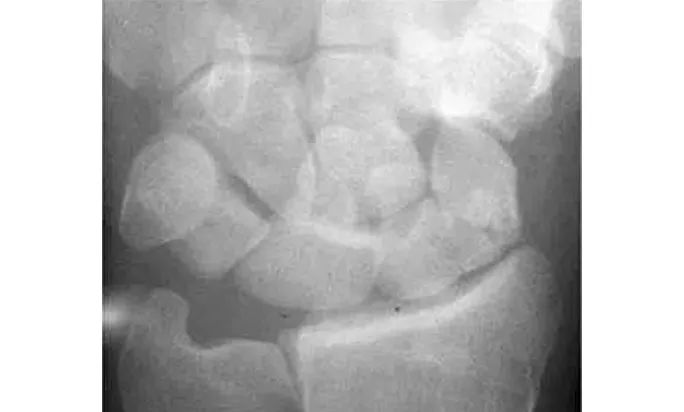

Case 分析

舟骨-大多角骨-小多角骨关节(STT关节)、第1腕掌关节(CMC1关节)严重骨关节病伴半脱位,掌骨弧线正常、平行关系存在。舟骨变长提示其向背侧倾斜。

侧位片示月骨也向背侧倾斜,近排腕骨作为一个整体移动,所以不存在脱位。

最后诊断:无脱位DISI(背屈不稳)伴STT关节骨关节病及半脱位。